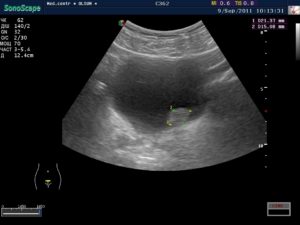

- УЗИ – метод позволяет определить размер, форму и локализацию опухоли, однако малоинформативен в отношении природы и характера образования. Данный способ целесообразно дополнить компьютерной томографией.

- исследование мочевого пузыря с помощью ультразвука – показывает участок поражения, размер образования и вид;